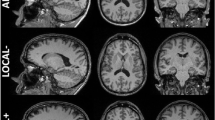

Figure 4 (upper panel) shows the test–retest RE (average and standard deviation of RE across the whole group) for each hippocampal subfield segmentation (left and right hemisphere averages) separately for the three pipelines.

Test–retest volume reproducibility error (upper panel) and spatial reproducibility (DICE coefficient, lower panel) of whole hippocampus and its subfields for the three tested segmentation pipelines (long_T1s, long_T1s_FLAIR and long_T1s_FLAIR_crossT2). The last region on the right is relative to the structure obtained merging the whole hippocampus and fissure. Error bars represent the standard deviation from the mean. CA1, CA2-3, CA4 cornu ammonis areas, GC-ML-DG granule cells in the molecular layer of the dentate gyrus, HATA hippocampal-amygdala transitional area, Hp_ML molecular layer, Fissure hippocampal fissure, Hp_Tail hippocampal tail

RE varies across hippocampal structures from 1 to 6% (Fig. 4, upper panel, red bars). In particular, mean test–retest RE among MRI sites was ≈1% and ≈0.9% for Whole_Hp and Whole_Hp_Fiss, respectively. With regard to the hippocampal subfields, the mean test–retest RE was ≈6% for fissure, < 5% for fimbria, ≈3% for parasubiculum, < 3% for HATA, and < 2% for the other structures.

The DICE coefficients of spatial overlap can be seen in the lower panel of Fig. 4 (red bars, long_T1s_FLAIR pipeline). The spatial reproducibility (DICE) was ≈ 95.2% for Whole_Hp_Fiss, ≈93.9% for Whole_Hp, ≈ 93.5% for Hp_Tail, > 85% for subiculum, presubiculum, CA1, and CA4, > 80% for parasubiculum and HATA, > 75% for GC-ML-DG, Hp_ML, CA2-3, and fimbria, ≈61% for the fissure.

Figure 5 shows the distribution of test–retest reproducibility metrics as functions of hippocampal structure volume. The RE distribution (Fig. 5, top), shows a fairly stable reproducibility in the range of 1–2% for structures larger than 200 mm3, with reproducibility loss for smaller structures (fissure, fimbria, parasubiculum, HATA). The DICE coefficient distribution (Fig. 5, bottom), shows an overall good spatial reproducibility (75–95%) across volumes except for the fissure.

Test–retest volume reproducibility error (upper panel) and spatial reproducibility (DICE coefficient, lower panel) of hippocampal subfields obtained from the long_T1s_FLAIR pipeline as a function of the structure volume. The volumes were averaged across hemispheres, sessions, and subjects. CA1, CA2-3, CA4 cornu ammonis areas, GC-ML-DG granule cells in the molecular layer of the dentate gyrus, HATA hippocampal-amygdala transitional area, Hp_ML molecular layer, Fissure hippocampal fissure, Hp_Tail hippocampal tail

The post hoc Wilcoxon test showed a significant decrease of hippocampal structures reproducibility in the long_T1s_FLAIR_crossT2 pipeline with respect to the other two longitudinal pipelines, both in terms of RE and DICE coefficient (p < 0.001 in all cases). The higher reproducibility of the longitudinal pipelines can be seen in Fig. 4 (upper panel). Except for the hippocampal fissure, there was an average reduction of 0.4–3.6% in the test–retest RE of all segmentations. Similarly (Fig. 4, lower panel), with regard to the reproducibility of spatial overlap of the segmentations, the longitudinal pipelines showed a higher spatial reproducibility (1.1–7.8% of DICE improvement) in all hippocampal structures relative to the long_T1s_FLAIR_crossT2 pipeline.

Moreover, when comparing the two longitudinal pipelines, long_T1s_FLAIR provided a small but significant reproducibility improvement in terms of test–retest RE (Wilcoxon test, p = 0.015). Meanwhile, no significant DICE differences were found between the two longitudinal pipelines (Wilcoxon test).